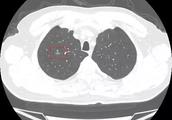

Examination of a lot of human body went out " liver cyst " , thought cancer of the liver is euqally acedia, actually can need not.

Liver cyst is congenital mostly, namely " of mother's womb inner tube " , and grow very special and slow, most person is not to have apparent symptom more. If not be,discover accidentally when check-up, some people won't discover all one's life even.

According to Sichuan Doctor Peng Wei introduces surgery of courage of courtyard of university China Western medicine, check-up checks cyst giving liver, need not worry mostly. Majority liver cyst does not need medicaments or operation treatment, need the fixed observation that follow examine only.

Only one fraction person needs a surgery, include among them: Cyst diameter > 8.0cm has clinical symptom; Cyst is amalgamative haemorrhage, infection; Cyst cannot be in charge of adenoma to differentiate with courage; Disease of much bursa liver brings about the person that door pulse maximum pressure and function are damaged.